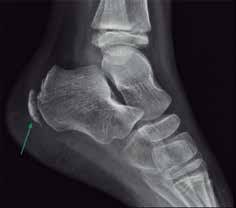

La radiografía simple en proyecciones lateral y dorsoplantar se utiliza principalmente para descartar patologías óseas de mayor gravedad. Aunque la esclerosis y fragmentación de la apófisis son hallazgos radiográficos clásicos asociados a esta enfermedad, carecen de especificidad por ser variantes normales del desarrollo en muchos niños asintomáticos. No obstante, en cuadros clínicos refractarios que superan las seis semanas de evolución, la resonancia magnética constituye la herramienta más sensible para confirmar el diagnóstico al evidenciar edema de médula ósea en la zona afectada.